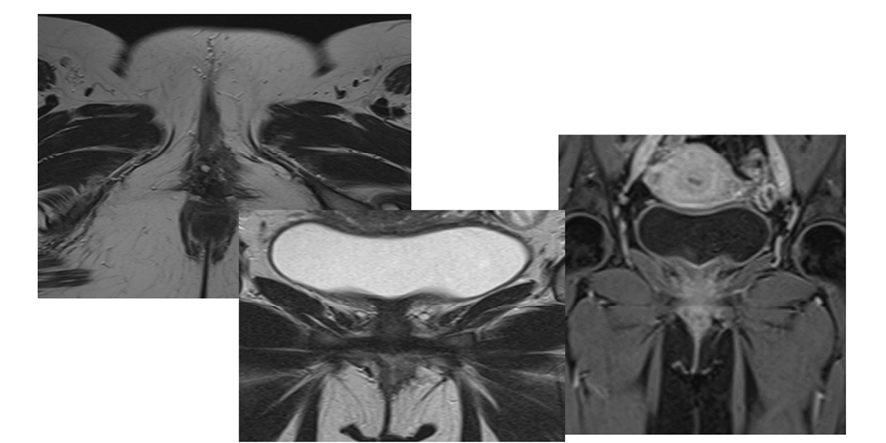

Two months postoperatively, an MRI Post-resection images show complete resection with no feasible scar, residual tumor, or recurrence. There is no vaginal wall deformity. Post-contrast shows no significant abnormal enhancement (Figure-4). Incision site healing was unremarkable, and the patient reported no new symptoms.

Figure 4. Post-contrast shows no significant abnormal enhancement.